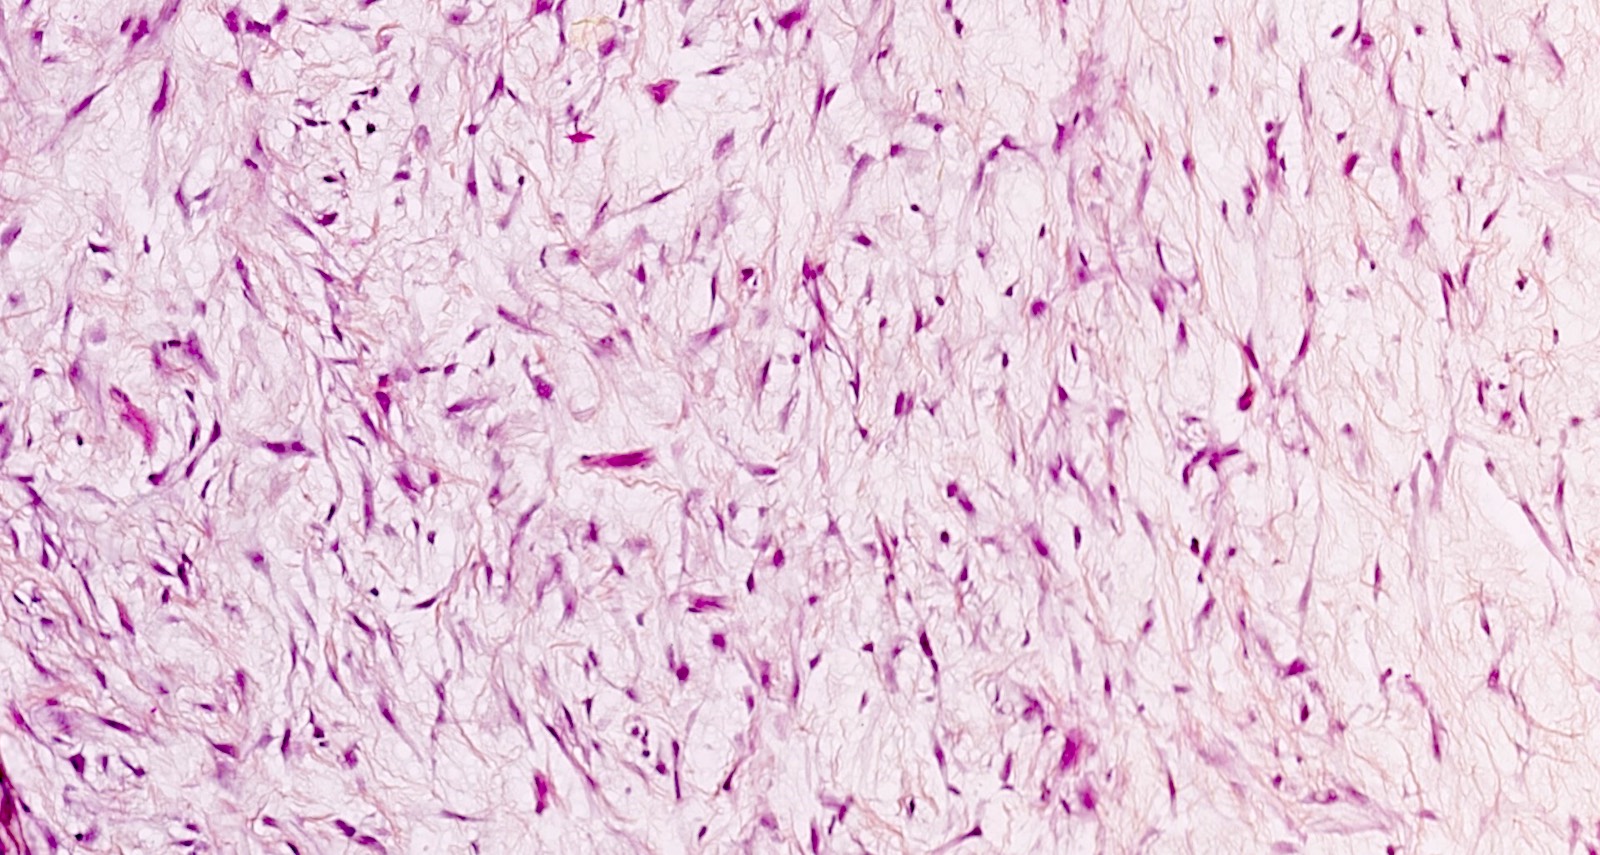

leiomyosarcoma myxoid tumor infiltrative growth leiomyoma necrosis tumors myometrium hypocellular abundant uterus eosin minimal atypia hematoxylin magnifications

leiomyoma myxoid change pathology webpathology comments

uterus myxoid leiomyoma muscle smooth webpathology pathology fibrillary cells nuclei comments

myxoid leiomyoma smooth cells muscle